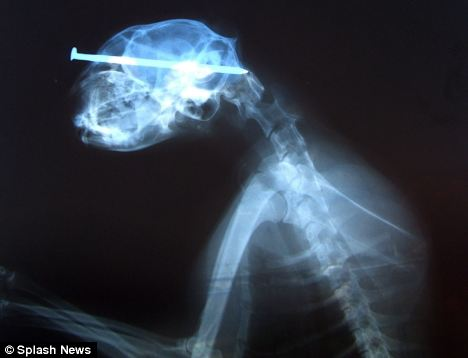

當(dāng)時(shí)照的X光圖

雖然人人都說貓有9條命,但是看到小貓“奇異恩典”頭插8厘米鐵釘在街頭漫步時(shí)你一定還會(huì)驚嘆,貓的生命力真是太強(qiáng)大了!

據(jù)英國(guó)媒體5月25日?qǐng)?bào)道,“奇異恩典”生活在美國(guó)艾奧瓦州西部港口城市蘇城,盡管頭部被一個(gè)惡棍插進(jìn)去了8厘米長(zhǎng)的鐵釘,但它卻什么事兒也沒有,還好端端地在街頭閑逛。

最終,有人發(fā)現(xiàn)了小貓頭部的異物,并將它送到了獸醫(yī)那兒。經(jīng)過手術(shù),獸醫(yī)將它頭上的鐵釘成功拔出。為小貓主刀的辛迪?拉萊特醫(yī)生稱:“我從來沒見過這樣的事,受這么重的傷居然還能和沒事一樣,太神奇了?!?/font>